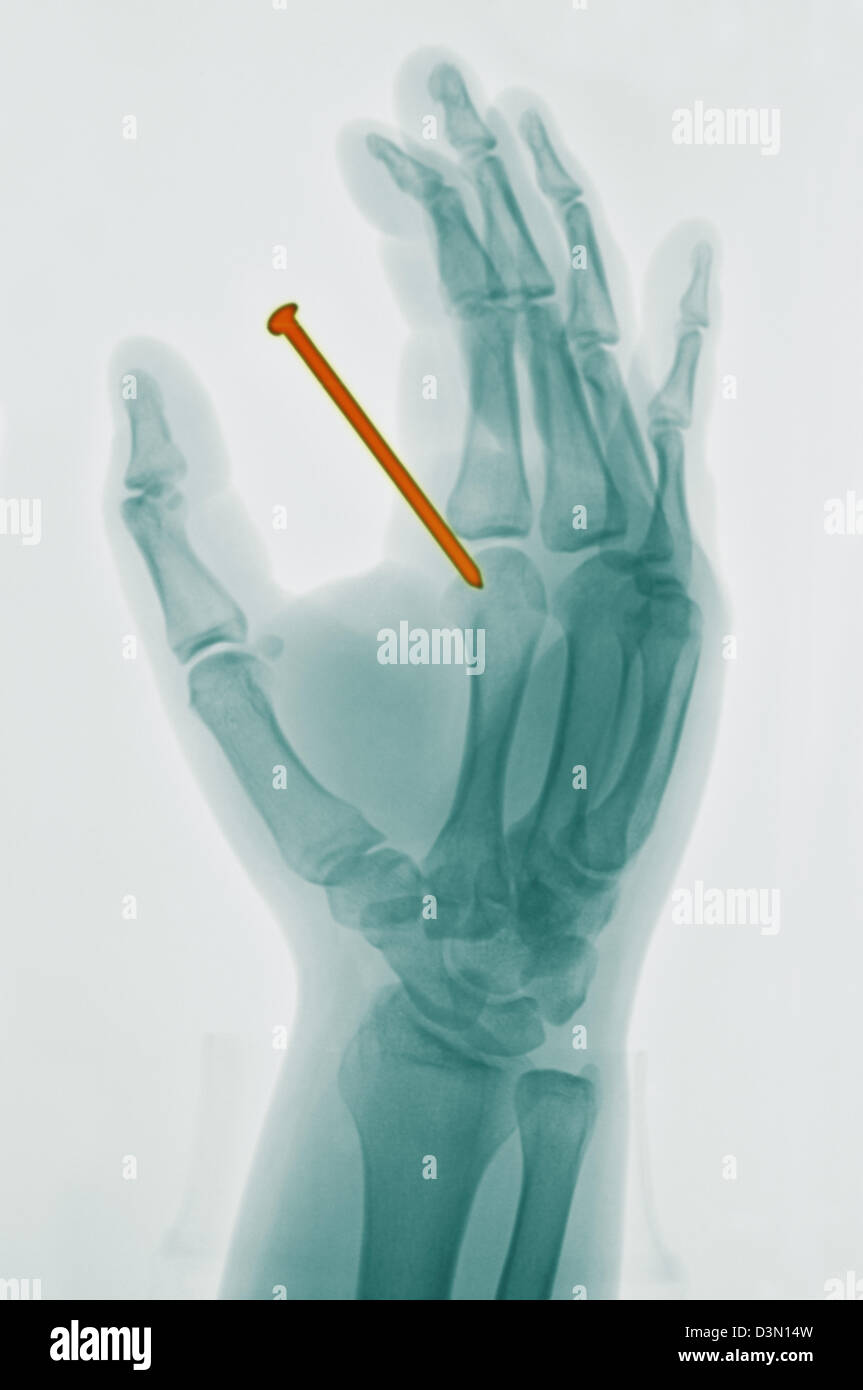

hand xray of a 26 year old man who accidentally shot a nail from a Nail Gun Through Finger Nail gun injuries, common in the construction industry, are usually puncture wounds on the hands and fingers, but sometimes they result in. The guidance highlights what is known about nail gun injuries, including the parts of the body most often injured and the types of severe injuries. Most injuries to the nail arise from one of three mechanisms. Evaluation and. Nail Gun Through Finger.

hand xray of a 26 year old man who accidentally shot a nail from a Nail Gun Through Finger Accidental discharge, careless handling of equipment, overpenetration of structures by the nail, ricochet or shattering of the nail, or structural unsoundness of the receiving. Penetrating injuries cause considerable pain and discomfort to the patient, effective analgesia needs to be provided to allow removal of object, investigations and cleaning of the wound. Nail gun injuries, common in the construction industry, are. Nail Gun Through Finger.